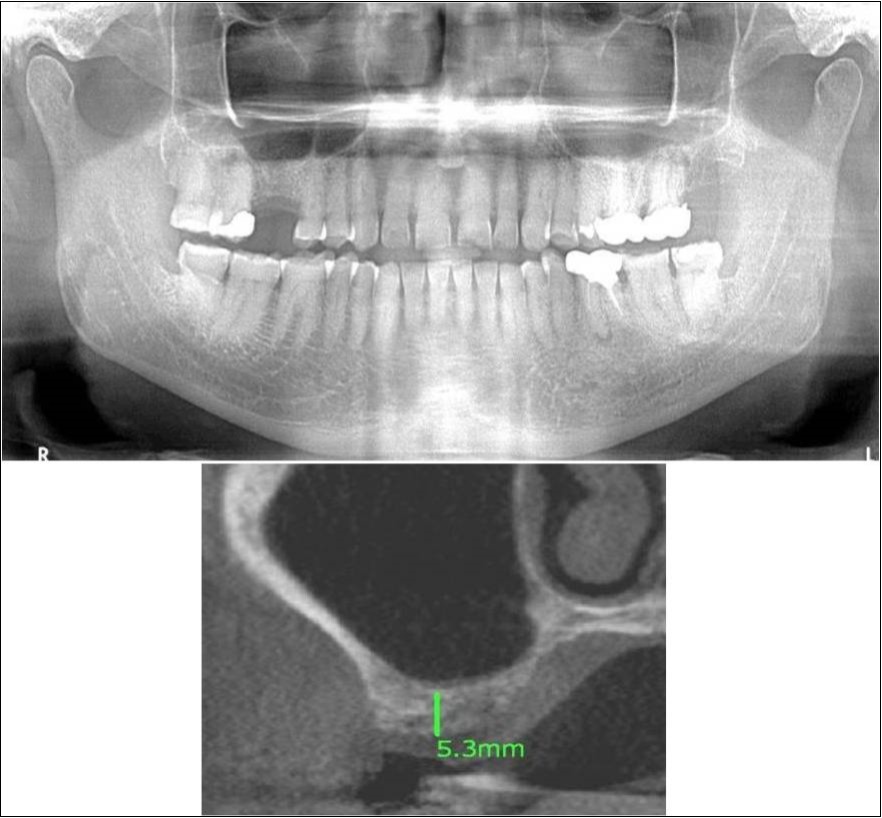

Case Report 1:

A 40 years old male patient reported to the Department of Oral and Maxillofacial Surgery, D.A.P.M.R.V Dental College and Hospital with a chief complaint of inability to chew food because of loose teeth from past one year. The teeth were extracted an year ago in the right upper and lower back tooth regions because of gross loss of tooth structure and poor prognosis for root canal treatment. Patient was a controlled diabetic and was on medication for the same. Patient did not give history of any existing sinus pathologies. All possible rehabilitative options were explained to the patient and a treatment plan of replacement of missing teeth with implant supported prosthesis using two dental implants was finalized.

Clinical and Radiological Assessment:

1.Partially edentulous maxillary and mandibular arches with missing 16, 17, 18, 46, 47, 48;

2.Increased pneumatisation of right maxillary sinus;

3.Chronic generalized periodontitis;

4.Inter-ridge space adequate to place implant (25mm).

Treatment: Direct sinus augmentation using calcium phosphosilicate (CPS) in relation to 16,17 followed by implant placement as a single step procedure was advised. Lateral window was created and calcium phosphosilicate putty (2cc) was dispensed as the graft material through the lateral osteotomy site to maintain the elevated sinus membrane followed by placement of two dental implants through the crestal approach measuring 3.75 x 11.5mm under local anaesthesia and strict aseptic protocols. At the end of 6 months, a repeat CBCT scan was advised to evaluate the increase in bone height. (Figure 7a-c, pre-treatment; Figure 8a-c, post-treatment)

Figure 7.(a-c) Pre-treatment OPG and cross sections of CBCT showing residual alveolar bone height for Case No.1;

Clinical and Radiological Assessment:

1.Partially edentulous maxillary arch with missing 16;

2.Increased pneumatisation of right maxillary sinus;

3.Height of available bone- 5.3mm;

4.Transverse thickness of available bone (CBCT evaluation)- 10.2mm;

5.Inter-ridge space adequate to place implant (10mm).

Treatment:

Patient underwent the procedure of indirect sinus elevation using sinus osteotomes in relation to 16 region. Calcium phosphosilicate putty was dispensed as the graft material through the crestal osteotomy site to maintain the elevated sinus membrane followed by placement of a dental implant measuring 5 x 10mm under local anaesthesia and strict aseptic protocols. The implant was allowed to osseo-integrate for a period of six months during which the patient was followed-up periodically and was assessed for peri-implantitis, crestal bone loss and mobility. At the end of 6 months, a repeat CBCT scan was advised to evaluate the increase in bone height. (Figure 11a,b, pre-treatment; Figure 12a,b, post-treatment)

Figure 11.(a,b) Pre-treatment OPG and cross section of CBCT showing residual alveolar bone height for Case No.3